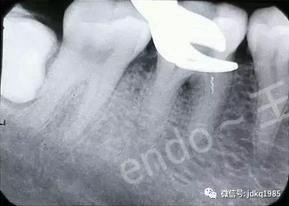

臨床病例報告:患者為30歲女性,因后牙自發(fā)性疼痛于當?shù)蒯t(yī)院行“根管治療”,治療過程中出現(xiàn)“斷針”,建議轉(zhuǎn)診,遂來我院就診。X線檢查可見46近中根管中上段約3mm的高密度影像,其余根管內(nèi)未見充填影像,根尖區(qū)見密度減低透射影。由于患者存在根尖病變,且分離器械位于根管中上段,因此我們給患者擬定了根管內(nèi)分離器械取出的治療方案。

術(shù)前X線片可見近中根管內(nèi)分離器械